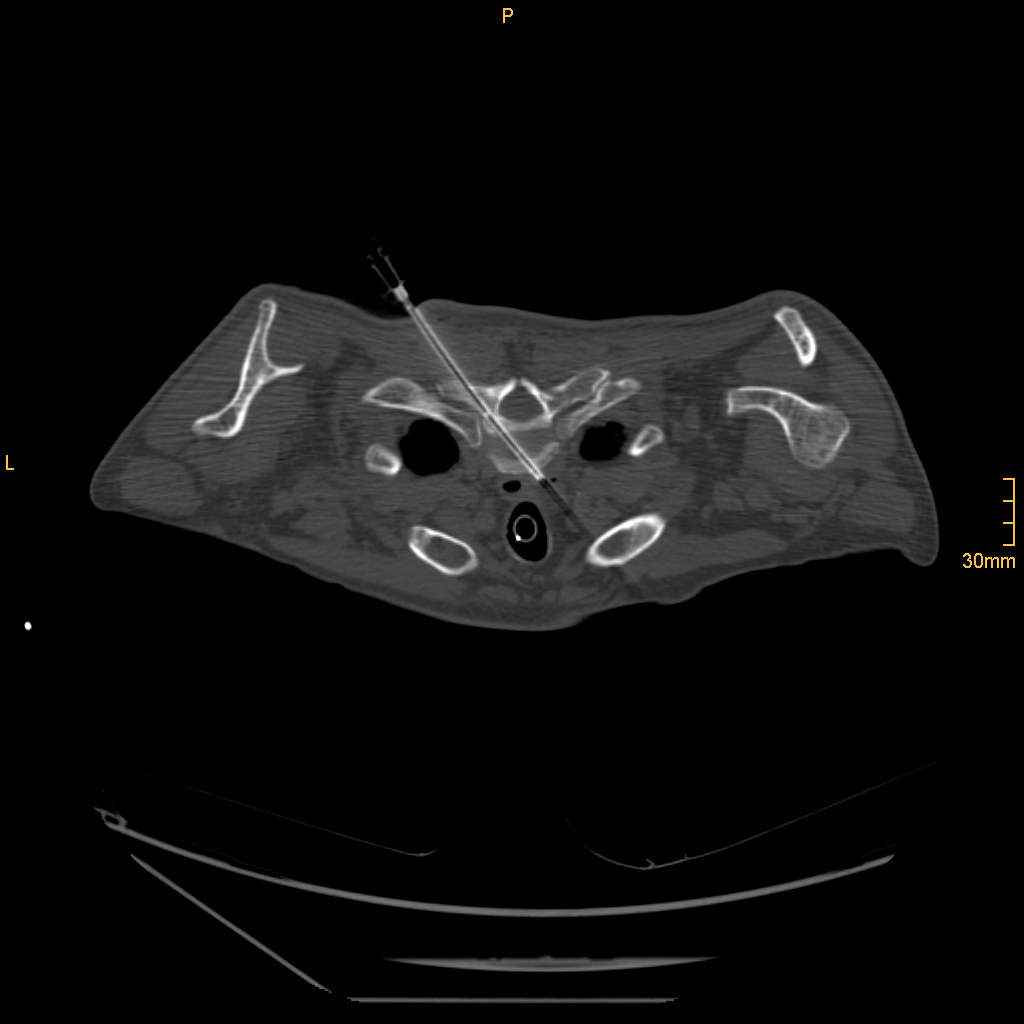

Nach Innsbruck kam Glodny aufgrund eines persönlichen Treffens mit o. Univ.-Prof. Dr. Werner Jaschke, dem Leiter der Innsbrucker Universitätsklinik für Radiologie. „Aus einem zunächst nur kurz angesetztem Termin bei ihm wurde ein mehrstündiges Gespräch, in dem ich erfahren habe, was hier in Innsbruck alles möglich ist und wie ich hier arbeiten kann“, erzählt Glodny rückblickend. Insbesondere die interventionelle Radiologie, durch die vielfältige therapeutische Eingriffe etwa in der Behandlung der arteriellen Verschlusskrankheit, oder von Blutungen oder Aneurysmen, von Tumoren- oder Metastasen möglich geworden sind, fasziniert den Radiologen und Forscher. „Mit durch Hochfrequenzstrom erzeugter Hitze, z. B. dem Verfahren der sogenannten Radiofrequenzablation, können Tumore oder Metastasen in Organen wie Leber, Niere oder Lunge behandelt werden. Die Vorteile dabei sind, dass ein oder mehrere Tumore extrem zielgenau und gründlich zerstört werden können, die ganze Prozedur aber für die PatientInnen sehr schonend ist. Die Absprache mit den behandelnden KollegInnen zur Erstellung eines individuellen interdisziplinären Behandlungskonzeptes für jede einzelne Patientin und jeden einzelnen Patienten garantiert die beste Versorgung.“ Am Standort Innsbruck schätzt Glodny vor allem das hohe fachliche Know How und gerät dabei nahezu ins Schwärmen: „Hier wird interventionelle Radiologie in absoluter Perfektion betrieben! Vor allem von Professor Reto Bale, der ein absoluter Experte auch in der Behandlung großer Tumore ist, kann ich sehr, sehr viel lernen. Darüber hinaus ist auch die Zusammenarbeit mit den KollegInnen aus der Universitätsklinik für Neuroradiologie unheimlich wertvoll und effektiv.“